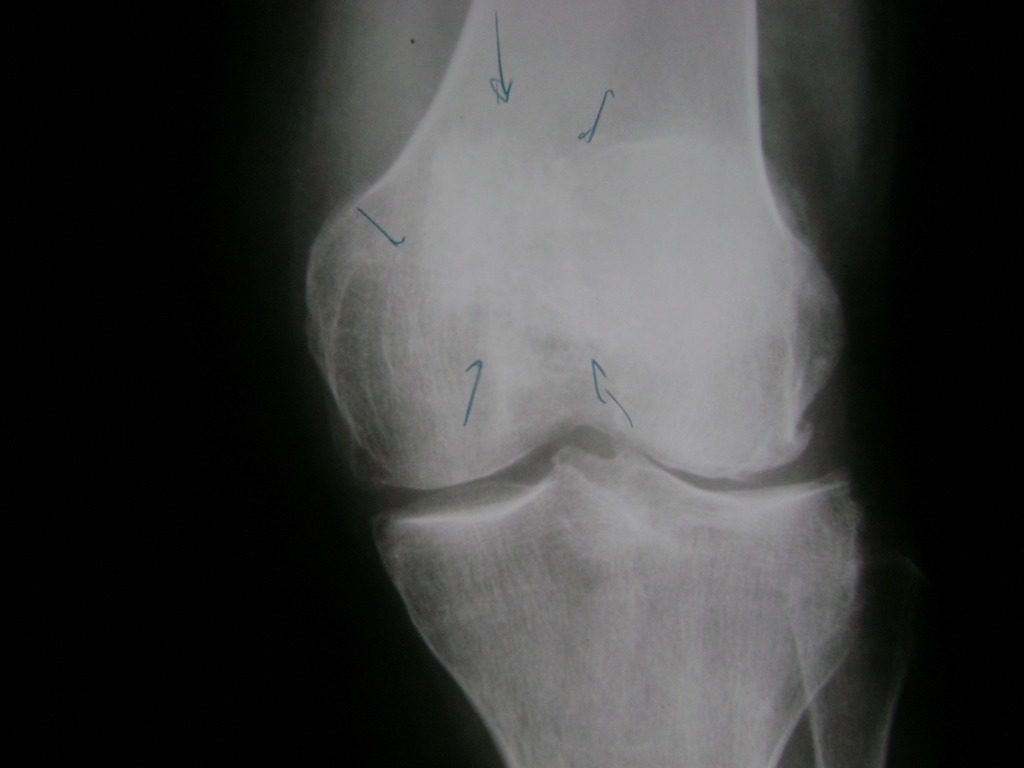

Cirugías de Codo - Rodilla

La artroscopia de rodilla es un cirugía en el cual la estructura interna de la articulación es examinada ya sea para realizar un diagnostico o para realizar un tratamiento, este procedimiento se realiza utilizando un instrumento parecido a un pequeño tubo llamado artroscopio.